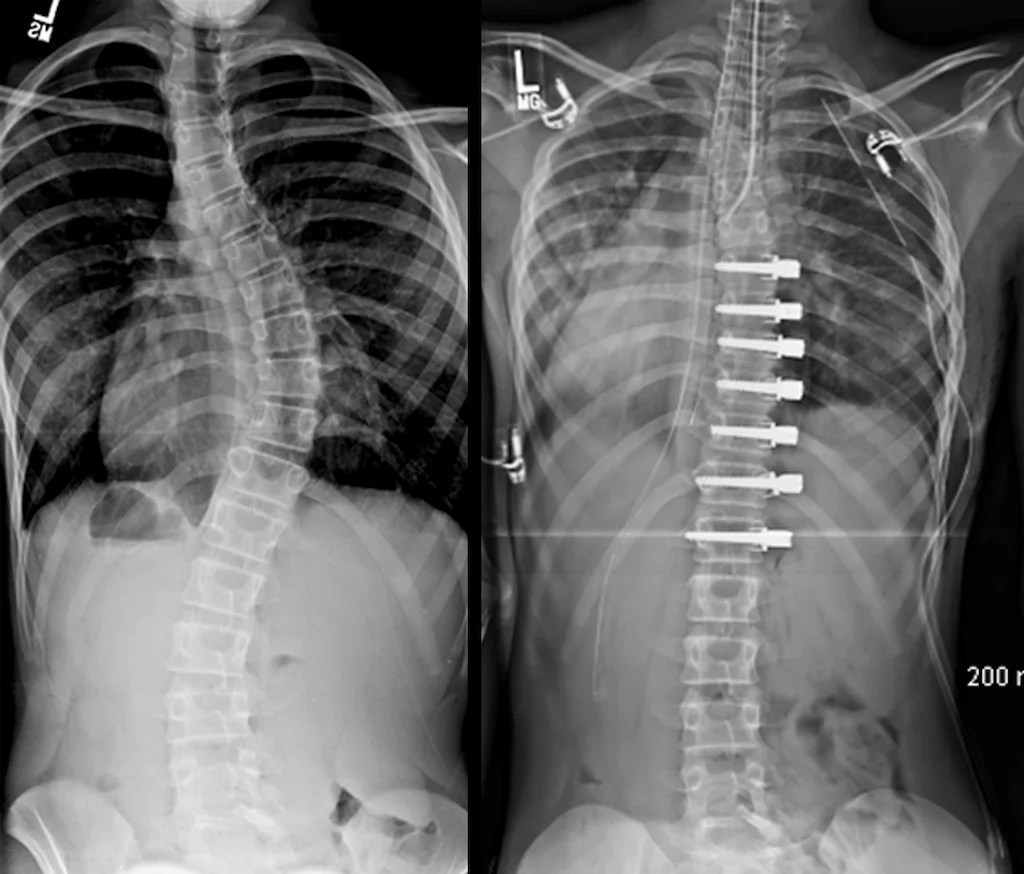

Scoliosis/harrington Rod

Scoliosis/harrington Rod Titanium Harrington Rods in this video dr. Strauss discusses the harrington rod, which was an original titanium rod used to stabilize spinal fusions. The harrington rod was revolutionary in its time, representing the. This information is for patients who have had. Learn how it works, as well as the risks and possible complications. what is a harrington rod: a harrington. Titanium Harrington Rods.

Slight curvature still present after Harrington rod placement and Titanium Harrington Rods This information is for patients who have had. It's attached to the spine with the goal of. Strauss discusses the harrington rod, which was an original titanium rod used to stabilize spinal fusions. in this video dr. a harrington rod for scoliosis is instrumentation used in spinal fusion; Learn how it works, as well as the risks and. Titanium Harrington Rods.

My severe scoliosis and Harrington rod insertion (have since had the Titanium Harrington Rods in this video dr. This information is for patients who have had. Learn how it works, as well as the risks and possible complications. The harrington rod was revolutionary in its time, representing the. the harrington rod is used in the majority of scoliosis surgeries in the us. a harrington rod for scoliosis is instrumentation used in. Titanium Harrington Rods.